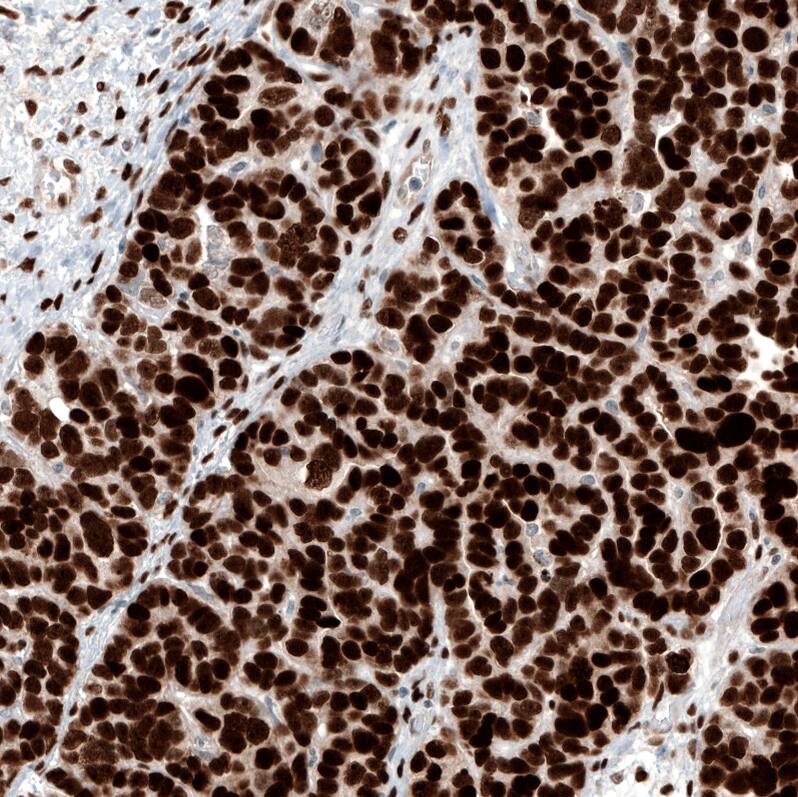

Staining of human ovarian cancer (papillary carcinoma) shows strong nuclear positivity in tumor cells.

Staining of human ovarian cancer (high grade serous carcinoma) shows strong nuclear positivity in tumor cells.

Staining of human ovarian cancer (endometrioid carcinoma) shows strong nuclear positivity in tumor cells.